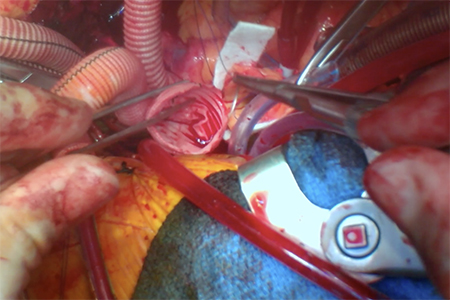

Vol 13, No 3 (May 31, 2024): Aortic Annular Enlargement